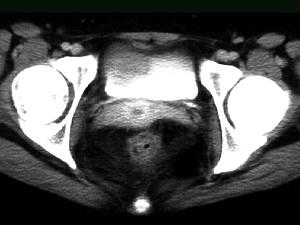

问题 女,32岁,腹痛、腹泻、便秘交替出现,黏液血便半年,里急后重,影像检查如图,最佳的诊断是 ( )

选项 A、溃疡性结肠炎 B、肠结核 C、慢性结肠炎 D、过敏性结肠炎 E、结肠癌

答案 A